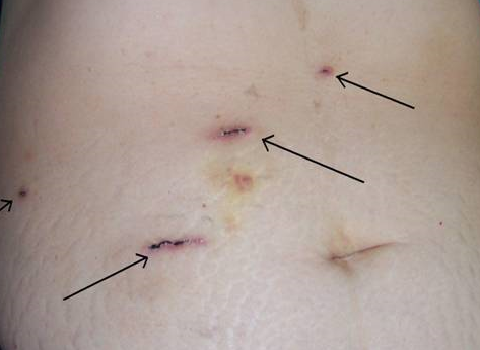

Laparoscopic Liver, Pancreas and Bilary Surgery

are advanced surgical procedures that requires adequate training in traditional open surgery as well as proficiency in laparoscopic techniques. Relevant and adequate training in step-wise manner up the ladder of complexity should be acquired by surgeons offering this approach coupled with adoption of modern instrumentation and equipment to ensure safe execution of the surgical procedures.

Such advance surgical procedures offered in GLAD Clinic include: